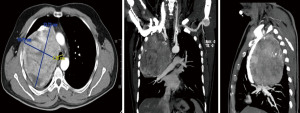

Further evaluation with an intravenous (IV) contrast-enhanced chest CT scan demonstrated a heterogeneous, enhancing hyper-vascular mediastinal mass located in the right paratracheal region.

The mass exhibited areas of cystic degeneration and calcification, along with an independent, normally located thyroid gland with a thyroid nodule (Figure 2). On the second hospital day, a CT-guided biopsy of the lesion was carried out, revealing positive immunohistochemical staining for thyroglobulin and thyroid transcription factor 1 (TTF-1), supporting a thyroid origin. Laboratory tests showed that thyroid-stimulating hormone (TSH) and serum free thyroxine (T4) levels were within normal parameters. These findings led to the diagnosis of ectopic thyroid tissue in the mediastinum. There were minimal diagnostic challenges in this case. However, due to the rarity of ectopic thyroid tissue in the mediastinum and the absence of symptoms, differential diagnoses such as lymphoma, thymic tumors, and metastatic lesions were considered. The high vascularity of the lesion also raised concern for potential biopsy-related bleeding, which was mitigated by careful image-guided biopsy. After obtaining informed consent, surgical resection was performed on the fifth hospital day via a right posterolateral thoracotomy. The patient was scheduled for surgical intervention. The procedure involved the use of a double-lumen endotracheal tube to achieve lung isolation, and the patient was positioned in the left lateral decubitus position. A right posterolateral thoracotomy was then carried out. Intraoperatively, the mass was found to be adherent to the lung parenchyma, posterior mediastinal pleura, right main bronchus, azygous and superior vena cava. The upper border of the gland lay below the 2nd rib. A complete surgical excision of the mass was achieved with the embedded azygous vein resected en-bloc, multiple arterial branches were ligated from the intercostal arteries, the patient was discharged home on postoperative day 3 (hospital day 8) and scheduled for outpatient follow-up at 2 weeks, 1 month, and 3 months postoperatively with chest X-ray.